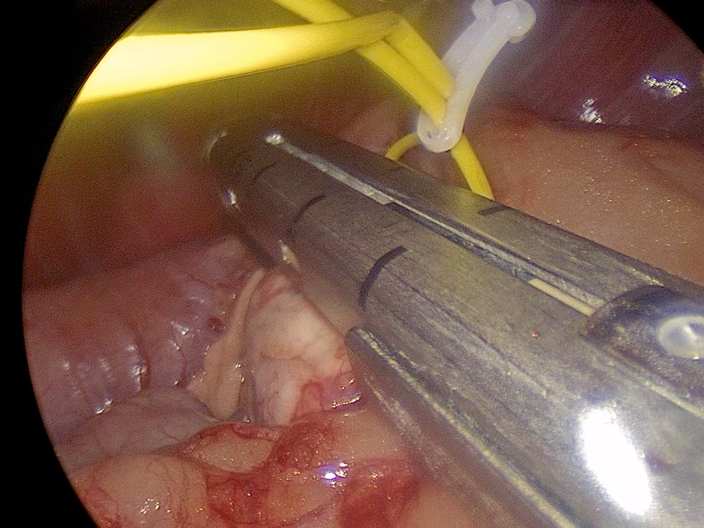

手術の様子

エンドGIAを用いての膵臓腫瘤摘出